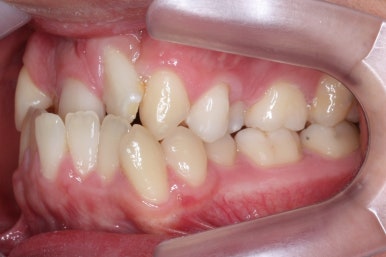

부산구순구개열 키다리아저씨치과에 처음 오셨을 때의 입 안의 모습입니다.

입천장이 갈라져서 어릴 때 봉합 수술을 했기 때문에 그 상처가 굵게 남아있는 것을 볼 수 있습니다. 일반적으로 피부상처도 다른 부위보다 단단하듯이 입천장의 봉합 상처도 매우 단단하게 아물기 때문에 성장에 방해를 주게 됩니다.

가로폭이 매우 좁고 찌그러져 있습니다.

또한 위턱이 앞으로 자라나는 것도 방해해 대부분 앞니가 거꾸로 물리게 됩니다.

또한 가랄져 있던 선에 걸쳐 있는 영구치 일부는 선천결손이 되는 경우가 많습니다.

이번 환자분도 이런 특징을 모두 갖고 계셨습니다.